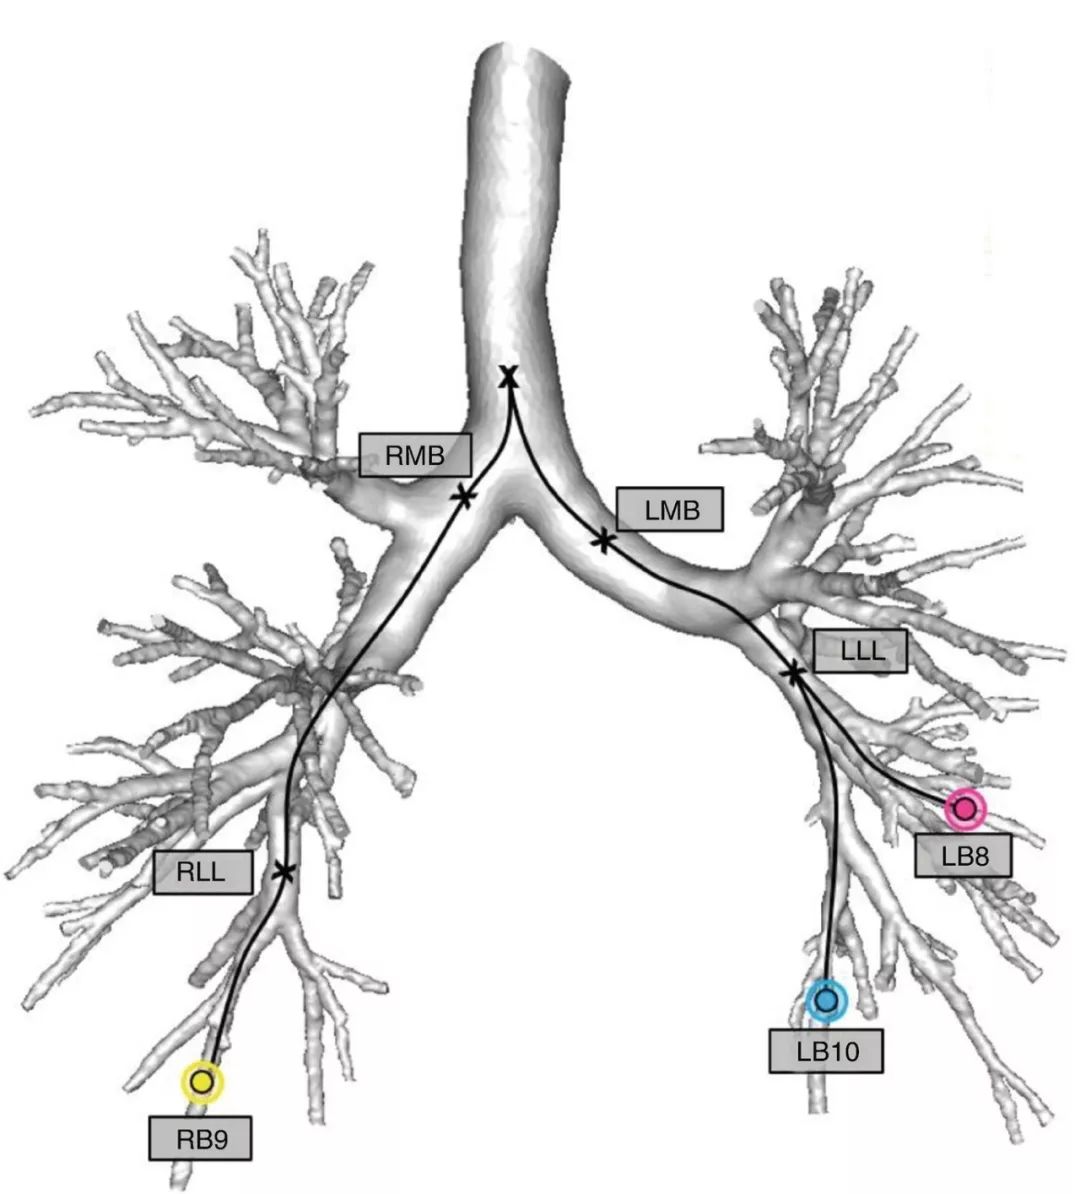

健培AI團隊提出了基于深度學習的3D氣管分割算法,利用人工智能技術,結合氣管樹3D解剖結構,從數據預處理,網絡結構模型,訓練策略,后處理等眾多方面進行優化。數據預處理方面結合臨床醫生經驗,設置了合理的肺部氣管樹形圖;針對氣管樹本身存在較大尺度變化,健培AI團隊設計了具有多尺度分割能力的3D卷積網絡模型,模型中集成了Google研究團隊提出的空洞卷積技術,有效的增強模型獲取肺部氣管樹語義信息的能力;采用難例挖掘技術訓練3D卷積網絡,并通過團隊自主設計的損失函數,最大限度的挖掘氣管樹的結構信息。